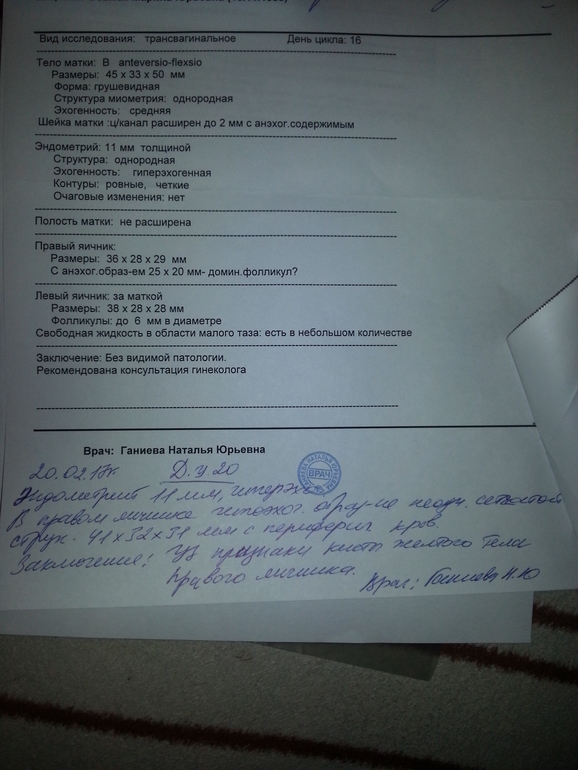

2-ая фолликулометрия

Девочки посмотрите пожалуйста!!!! Где ручкой написано -это сегодняшняя.Я что то не пойму ,была овуляция или нет? Что значит киста желтого тела? С такими значениями не получится забеременеть в этом цикле??? Объясните мне пожалуйста!!!))

20.02.2017